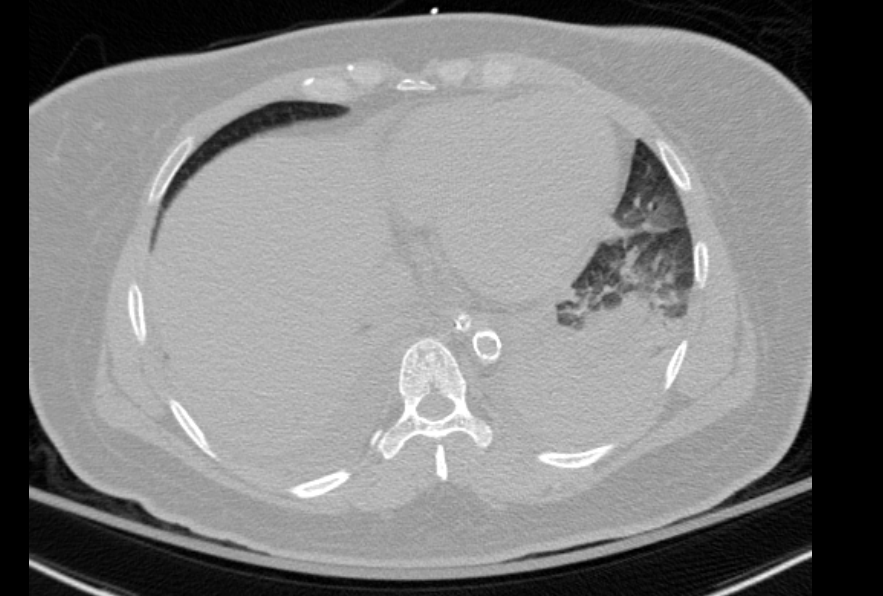

CT chest abdomen pelvis showed a calcified thrombus in the suprarenal aorta consistent with coral reef aorta.

She was initially thought to have ARDS secondary pulmonary infection, but CT showing the coarctation likley led to flash pulmonary edema secondary to hypertension due to the occlusion. Her renal failure was also secondary to hypoperfusion.